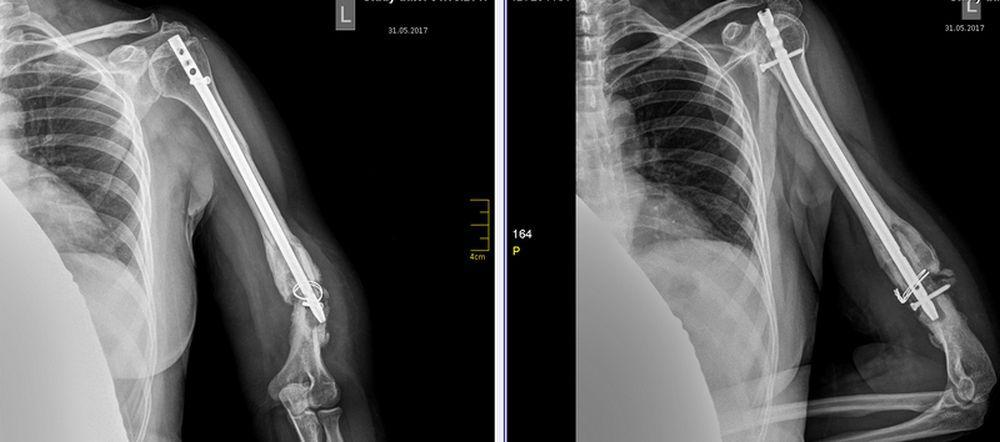

Псевдоартроз н/3 плеча после реЗИМО

Из анамнеза заболевания: травма 23.03.2016 , в результате падения на правый бок, обратилась в ГКБ по месту жительства, где был установлен диагноз: закрытый перелом нижней трети диафиза левой плечевой кости, в связи с чем была госпитализирована и 30.03.2016 выполнена операция: закрытый интрамедуллярный остеосинтез левой плечевой кости титановым плоским стержнем. В послеоперационном периоде беспокоили боли в нижней трети плеча, усиливающиеся при движении в смежных суставах, ограничение отведения и сгибания в левом плечевом суставе. На повторном приеме через 3 месяца установлен диагноз: псевдоартроз нижней трети диафиза левого бедра после остеосинтеза плоским стержнем.

В связи с чем была направлена в областную больницу, где 31.08.2016 выполнено удаление плоского стержня и реостеосинтез интрамедуллярным стержнем со статическим блокированием и серкляжем на уровне перелома. В послеоперационном периоде через 5 месяцев поле операции у пациентки появились жалобы на появление деформации в нижней трети диафиза. На повторном приеме в областной больнице рекомендовано исключить физ.нагрузки на левую руку, электрофорез с новокаином. Однако жалобы сохранялись. На повторном приеме через 4 месяца пациентке было рекомендовано обратится в наше отделение.

На момент осмотра через 10 месяцев после последней операции, пациентка предъявляет жалобы на боли в нижней трети диафиза левой плечевой кости, наличие видимой деформации и патологической подвижности на этом уровне. Локально: визуально определяется варусная деформация на уровне перелома, определяется укорочение левой плечевой кости относительно здоровой на 3см; пальпация в нижней трети левой плечевой кости умеренно болезненна, определяется крепитация в месте псевдоартроза, осевая нагрузка умеренно болезненна в плечевом суставе и нижней трети левого плеча, патологическая подвижность в н/3 плеча.

Диагноз: варусная деформация левой плечевой кости на фоне псевдоартроза на уровне нижней трети диафиза левой плечевой кости после реостеосинтеза интрамедуллярным стержнем со статическим блокированием и серкляжем, несостоятельность фиксации, хронический остеомиелит левой плечевой кости.